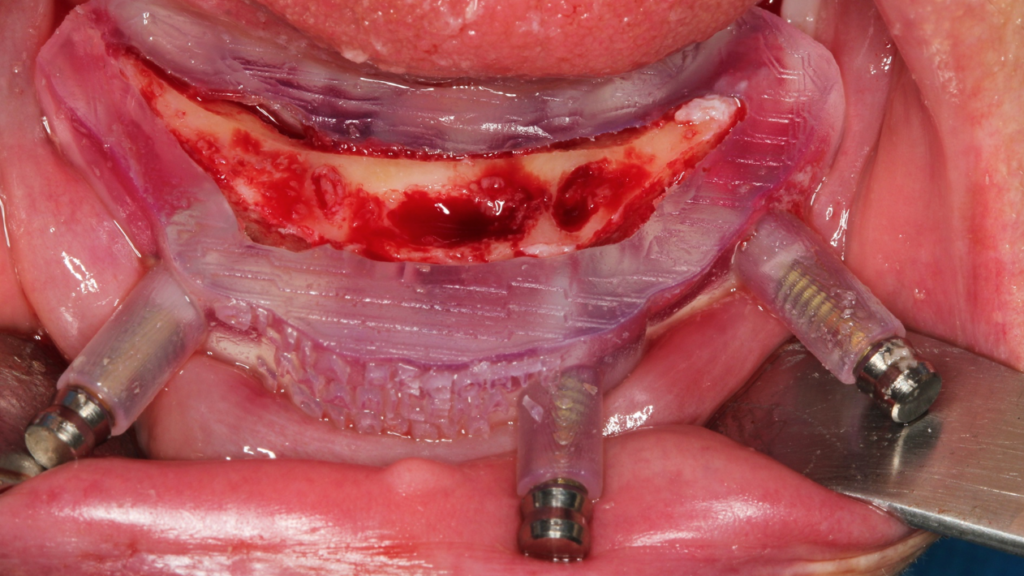

Através da imagem do osso recortado é planejada a guia de perfuração que vai se encaixar de uma maneira perfeita no osso recortado.

Lembrando que essas guias serão apoiadas exclusivamente no osso, sem envolvimento de mucosa, portanto há que se fazer incisão e descolamento mucoperiostal suficiente para o encaixe da guia.

O planejamento acima, foi feito para a instalação de uma prótese fixa aparafusada final, com estrutura metálica rígida e acrilização, no mesmo dia da cirurgia. A regularização do rebordo da paciente permitiu a instalação dos implantes em um posicionamento 3D ideal para uma reabilitação protética com os parâmetros biomecânicos, funcionais e estéticos adequados, transformando uma situação com várias limitações e dificuldades em um caso favorável, de uma maneira simples e previsível.